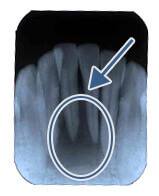

歯の周りのアゴの骨が溶けてなくなり膿が溜まっています(黒く写っている所)